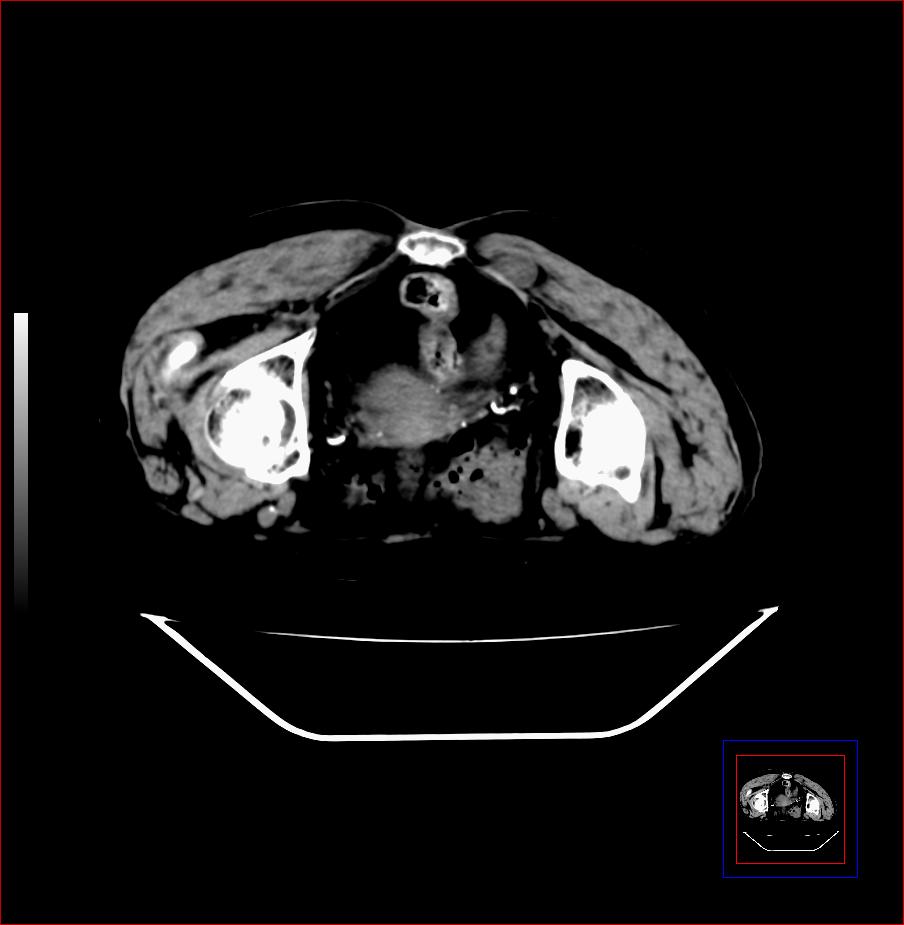

标题: CT17291:右侧臀大肌内可能是什么肿瘤(靠近尾骨那) [打印本页]

标题: CT17291:右侧臀大肌内可能是什么肿瘤(靠近尾骨那)

女,70岁,发现臀部包块2年,近日有压痛,无红肿热。

良性占位,纤维瘤可能性大,血管瘤不排除。建议增强ct或mr检查